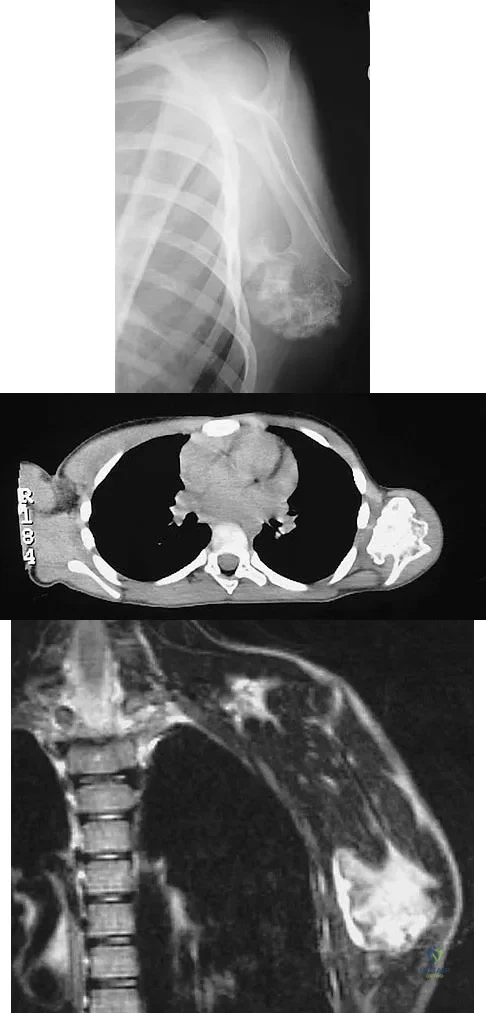

A 47-year-old woman has had left medial clavicle pain for the past 6 months. History is remarkable for mediastinal non-Hodgkin's lymphoma, treated with mantel radiation 22 years ago. A radiograph, CT scan, MRI scan, and a biopsy specimen are shown in Figures 68a through 68d. What is the most likely diagnosis?

Explanation